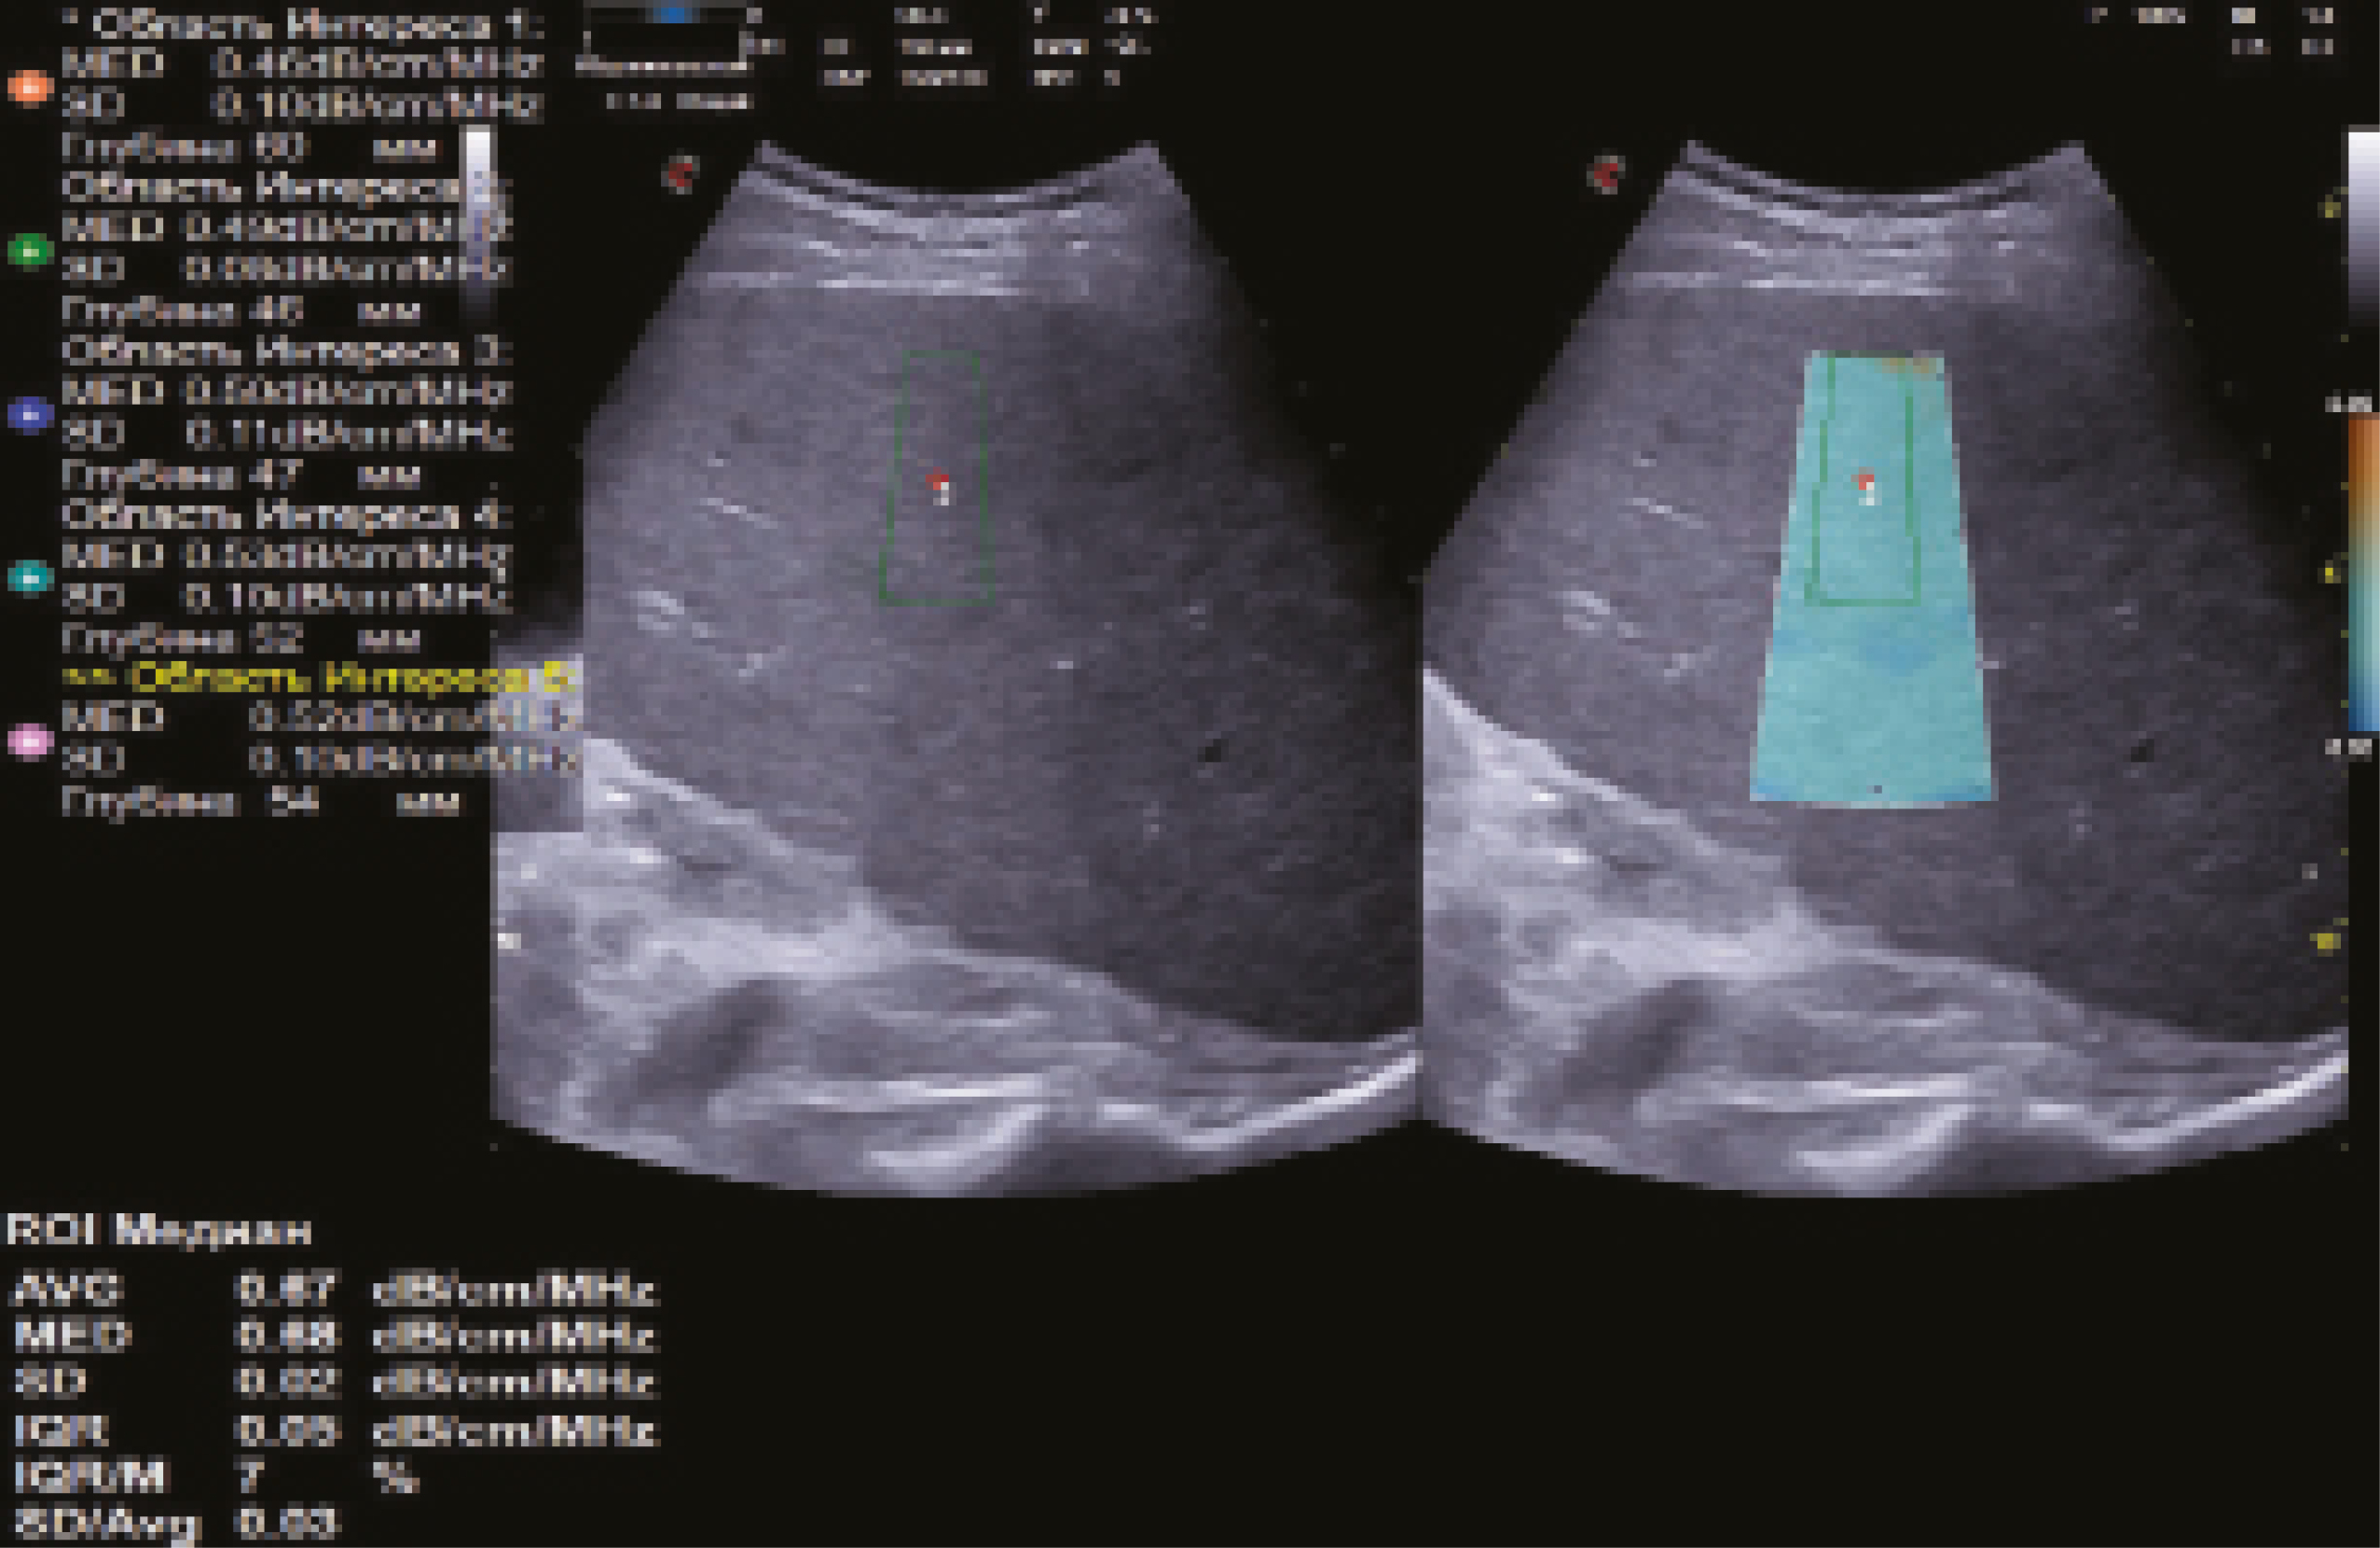

- использовать при наличии возможность сопоставления двух окон с единой визуализацией печени в В-режиме и в режиме количественной стеатометрии для дополнительного контроля;

- коррекция размера РИ: средняя ширина – 10–15 мм, большая длина – более 25 мм (для стандартизированной оценки коэффициента затухания УЗ-волны с вовлечением максимального объема ткани печени по глубине), не доходя нижней границей РИ до диафрагмы (оптимальная площадь РИ – 5–6 см2);

- центральное расположение РИ параллельно капсуле печени, на глубине не менее 10 мм (фиксация верхней границы РИ), под прямым углом к УЗ-лучам для минимизации количества артефактов;

- расположение РИ вдали от соседних органов и/или структур;

- определение среднего значения коэффициента затухания УЗ-волны по данным не менее 5 измерений;

- отношение интерквартильного размаха (IQR, interquartile range) к медиане (M, median) не более 30%.

Рис. 9. Эхограмма количественной ультразвуковой стеатометрии печени с определением коэффициента затухания ультразвуковой волны (0,67 дБ/см/МГц, стеатоз печени S1 – минимально выраженный), выполненная по правилам, предложенным авторами